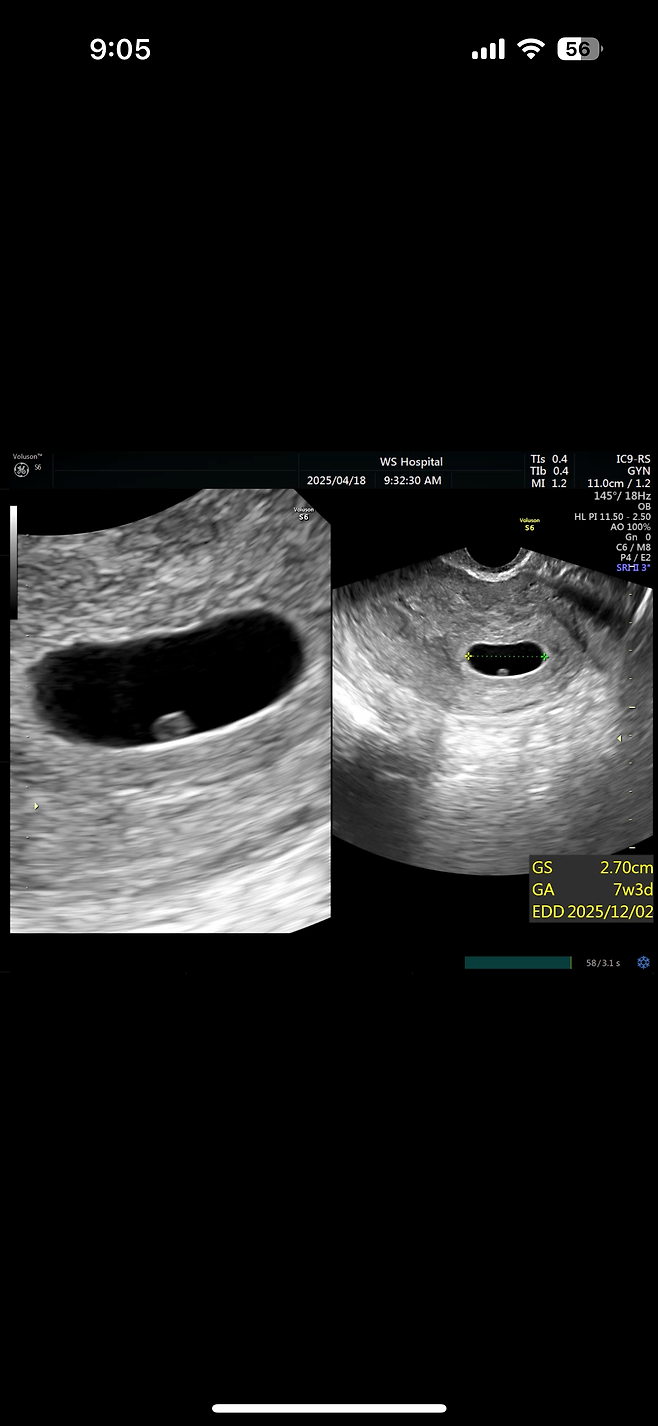

기다리던 아기라 너무너무 소중했는데

7주차에 하늘로 가네요.